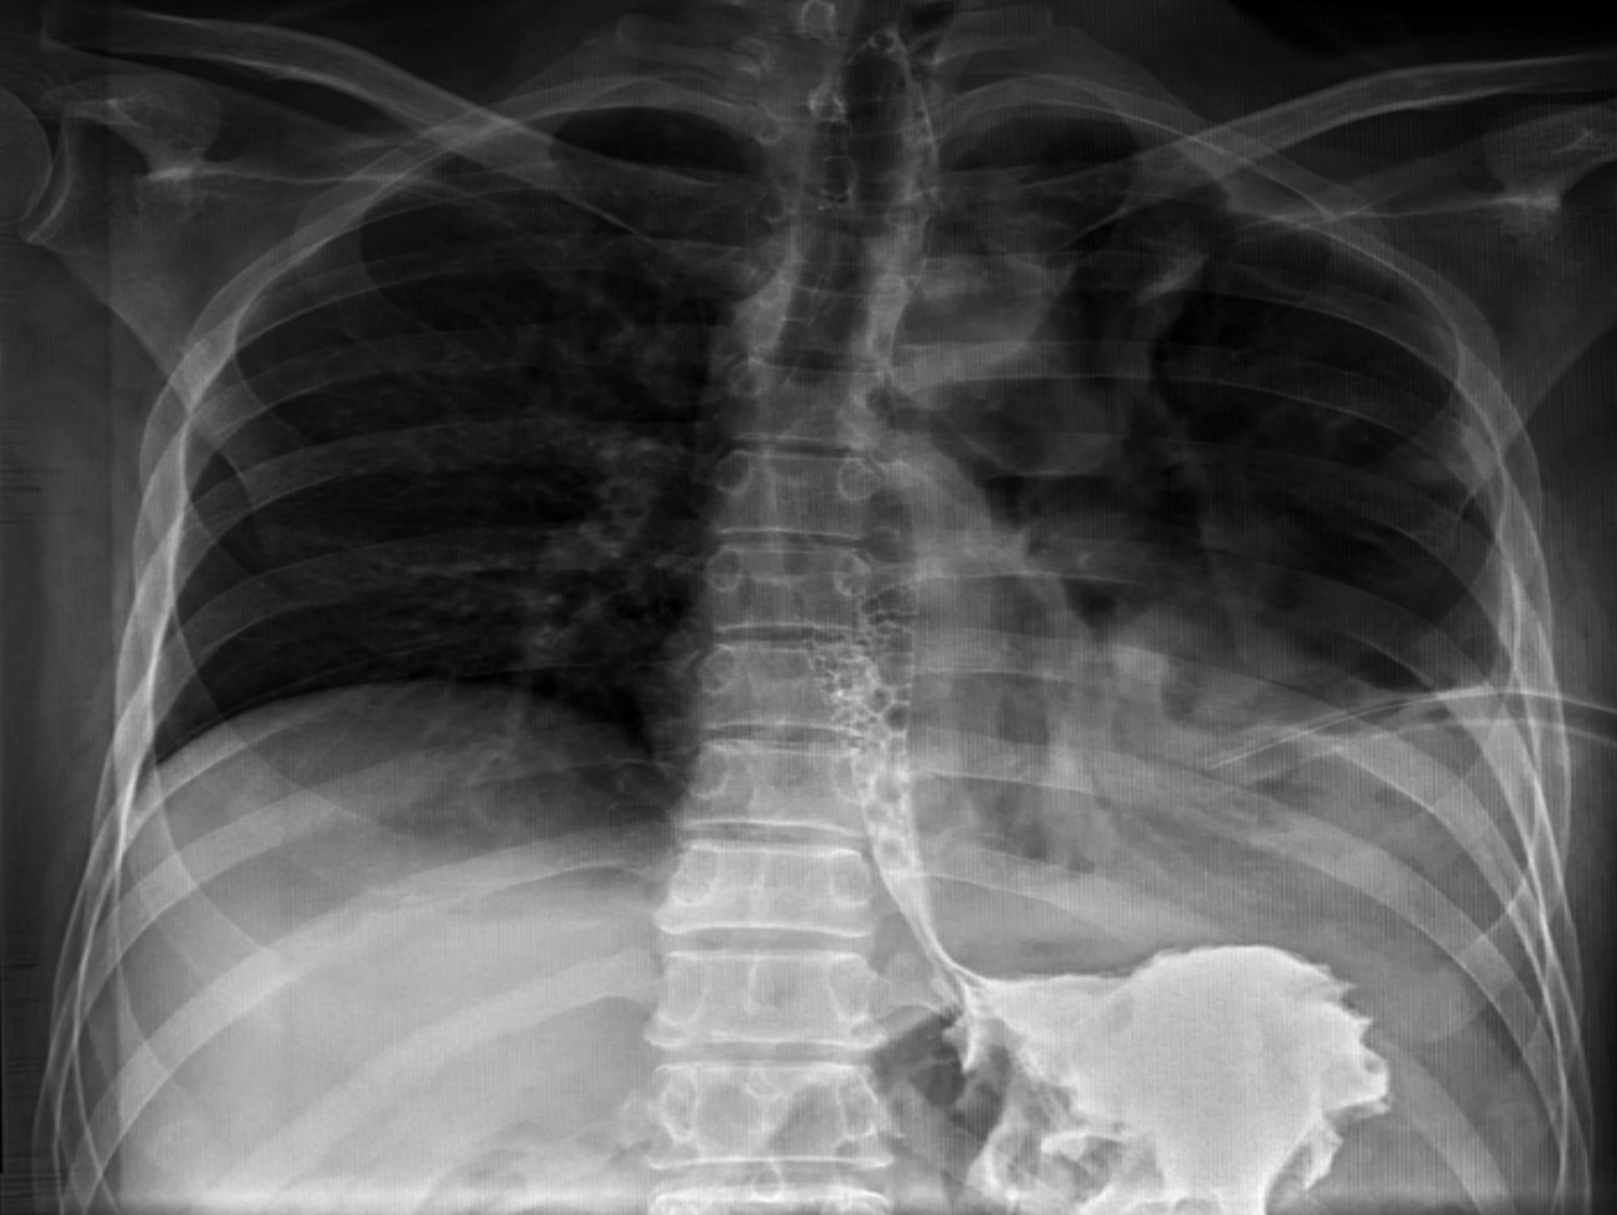

There was mild leucocytosis on laboratory investigations. A chest radiograph was immediately performed, which unveiled left-sided hydropneumothorax with mediastinal shift.

Initial clinical improvement was noted following chest tube insertion. However, soon after initiation of oral feed, food particles were noted in the drain. Barium swallow suggested GPF and diaphragmatic rupture (Figure 1). Computed tomography (CT) of the chest and abdomen revealed a large left pleural collection with air-fluid levels, discontinuity in the gastric fundus, and direct communication with the pleural space (Figure 2). No other intra-abdominal injuries were seen.